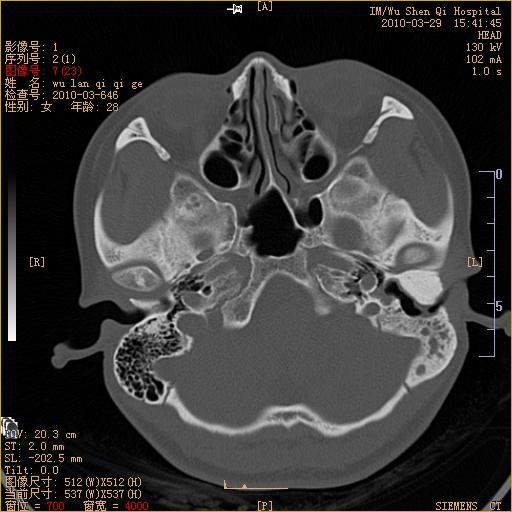

标题: CT25398:女,左耳流脓两年余,带有异物 [打印本页]

标题: CT25398:女,左耳流脓两年余,带有异物

左侧中耳乳突炎,不排除胆脂瘤形成。

左侧中耳乳突炎,胆脂瘤形成。

左侧中耳乳突炎,不排除胆脂瘤形成

1)左侧慢性中耳乳突炎并肉芽肿(或胆脂瘤)形成。2)考虑左侧颞骨慢性炎症伴骨质增生硬化,不排除骨纤。